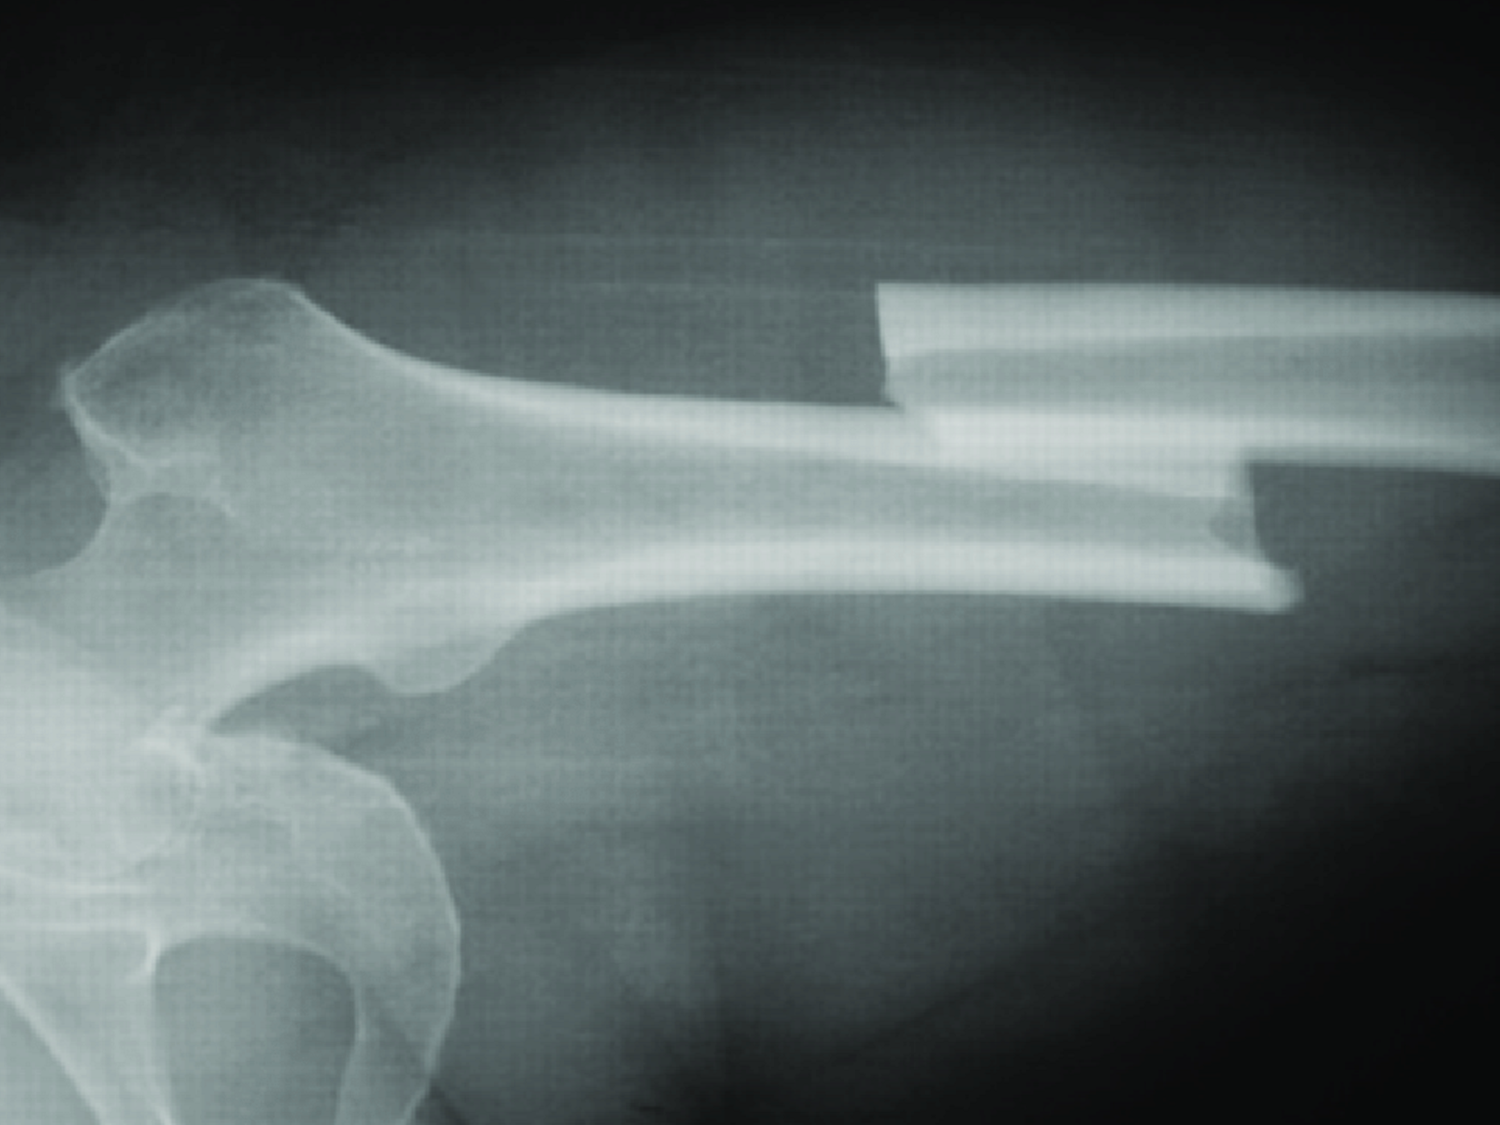

long bone - diaphysis

shaft of the long bone

6. diaphysis

long bone - epiphysis proximal

rounded ends of a long bone

-closer to the body center

1. Epiphysis (Proximal)

long bone- epiphysis distal

rounded ends of long bone

-farther away from center of body

4. Epiphysis (Distal)

long bone- spongy bone

Latticework of bone. Found in small flat bones, near the ends of long bones

5. Spongy bone

long bone- compact bone

dense outer layer with few internal spaces

2. Compact Bone

long bone- medullary cavity

inner most portion of the bone, where red and/or yellow bone marrow is located

3. Medullary Cavity